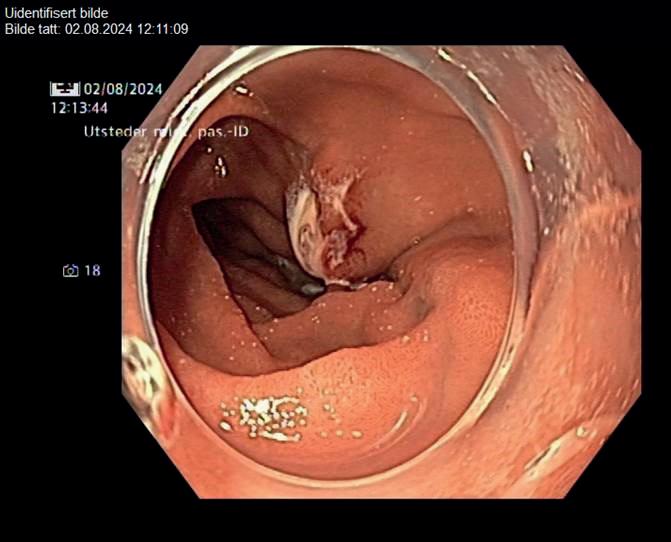

46 Bildequiz